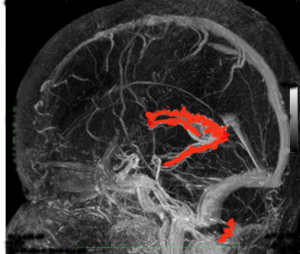

脳室内脈絡叢です(脳の静脈と一緒に描出しています)

正面から脈絡叢を見たところと左横から見たところ

- 髄液は脈絡叢(赤く塗ったところ)で作られます。

- 脈絡叢は側脳室と第3脳室と第4脳室にあります。下の方に離れているのが第4脳室のものです。